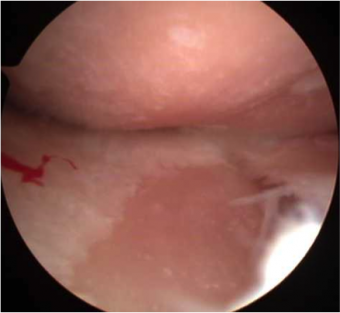

軟骨の磨耗像

軟骨が欠損し、骨が露出

高度の内反変形に対して人工膝関節全置換術(TKA)施行。

内側の軟骨は高度に欠損している(左:関節鏡所見)。